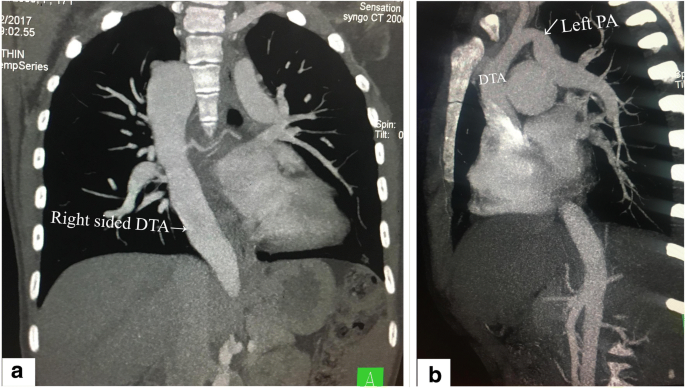

The murmur of aortic stenosis is heard and felt loudest in the 2nd intercostal space on the right side Figure 5 this is the area directly over the aorta 13. The new surgical journal seeks high-quality case reports small case series novel techniques and innovations in all aspects of vascular disease including arterial and venous pathology trauma arteriovenous. Right-sided aortic arch is a type of aortic arch variant characterized by the aortic arch coursing to the right of the trachea.

International Journal of Cardiology is a transformative journal. Different configurations can be found based on the supra-aortic branching patterns with the two most common patterns being the right-sided aortic arch with mirror image branching and the right-sided aortic arch with aberrant left subclavian artery. Double aortic arch is a relatively rare congenital cardiovascular malformation.